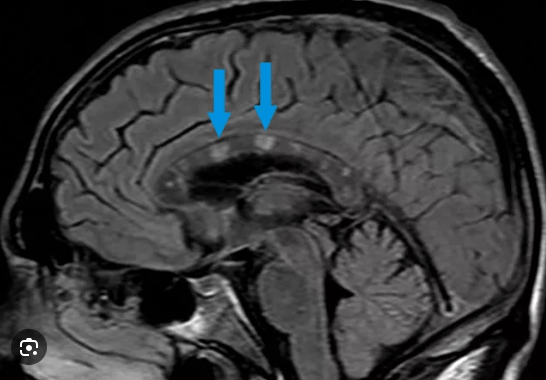

This condition causes ocular inflammation, audiovestibular symptoms, and lesions in the corpus callosum.

What is Susac's Syndrome